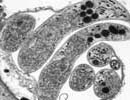

Cryptosporidium hominis UKH3

Courtesy of Saul Tzipori, Tufts

| Comment: | Cryptosporidium hominis is the dominant species which infects humans. Although generally self-limiting, this disease can cause fatalities in children and immunocompromised adults. The genome sequence of Cryptosporidium hominis shows features consistent with its life cycle as an obligate parasite. This organism lacks the genes necessary for the production of a number of biochemical building block such as nucleotides and amino acids. To compensate for this lack, the genome contains a large number of transporter or transporter-like genes. |